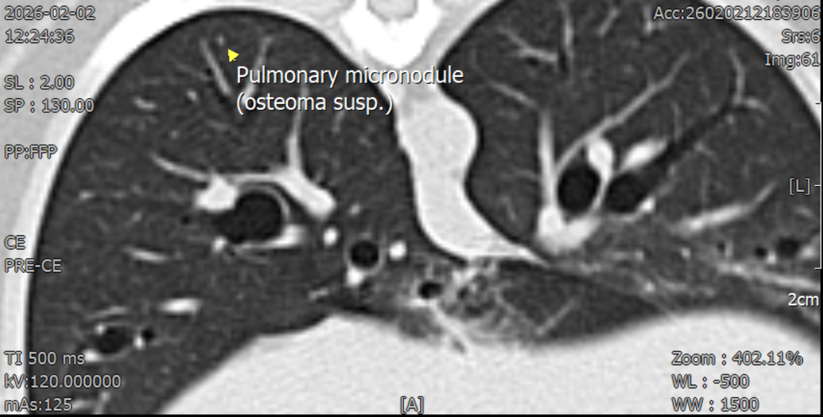

CT소견–좌측 신장 후극피질 유래의 크기 26mm*40mm의 조영 후 저감쇠성음영–간 좌측 안쪽엽에종괴가보이나 양성 병변 가능성이 더 높음–폐 우측 후엽의 미세결정 음영 CT검사상 전이 가능성은 상대적으로 낮은 상황이었습니다.